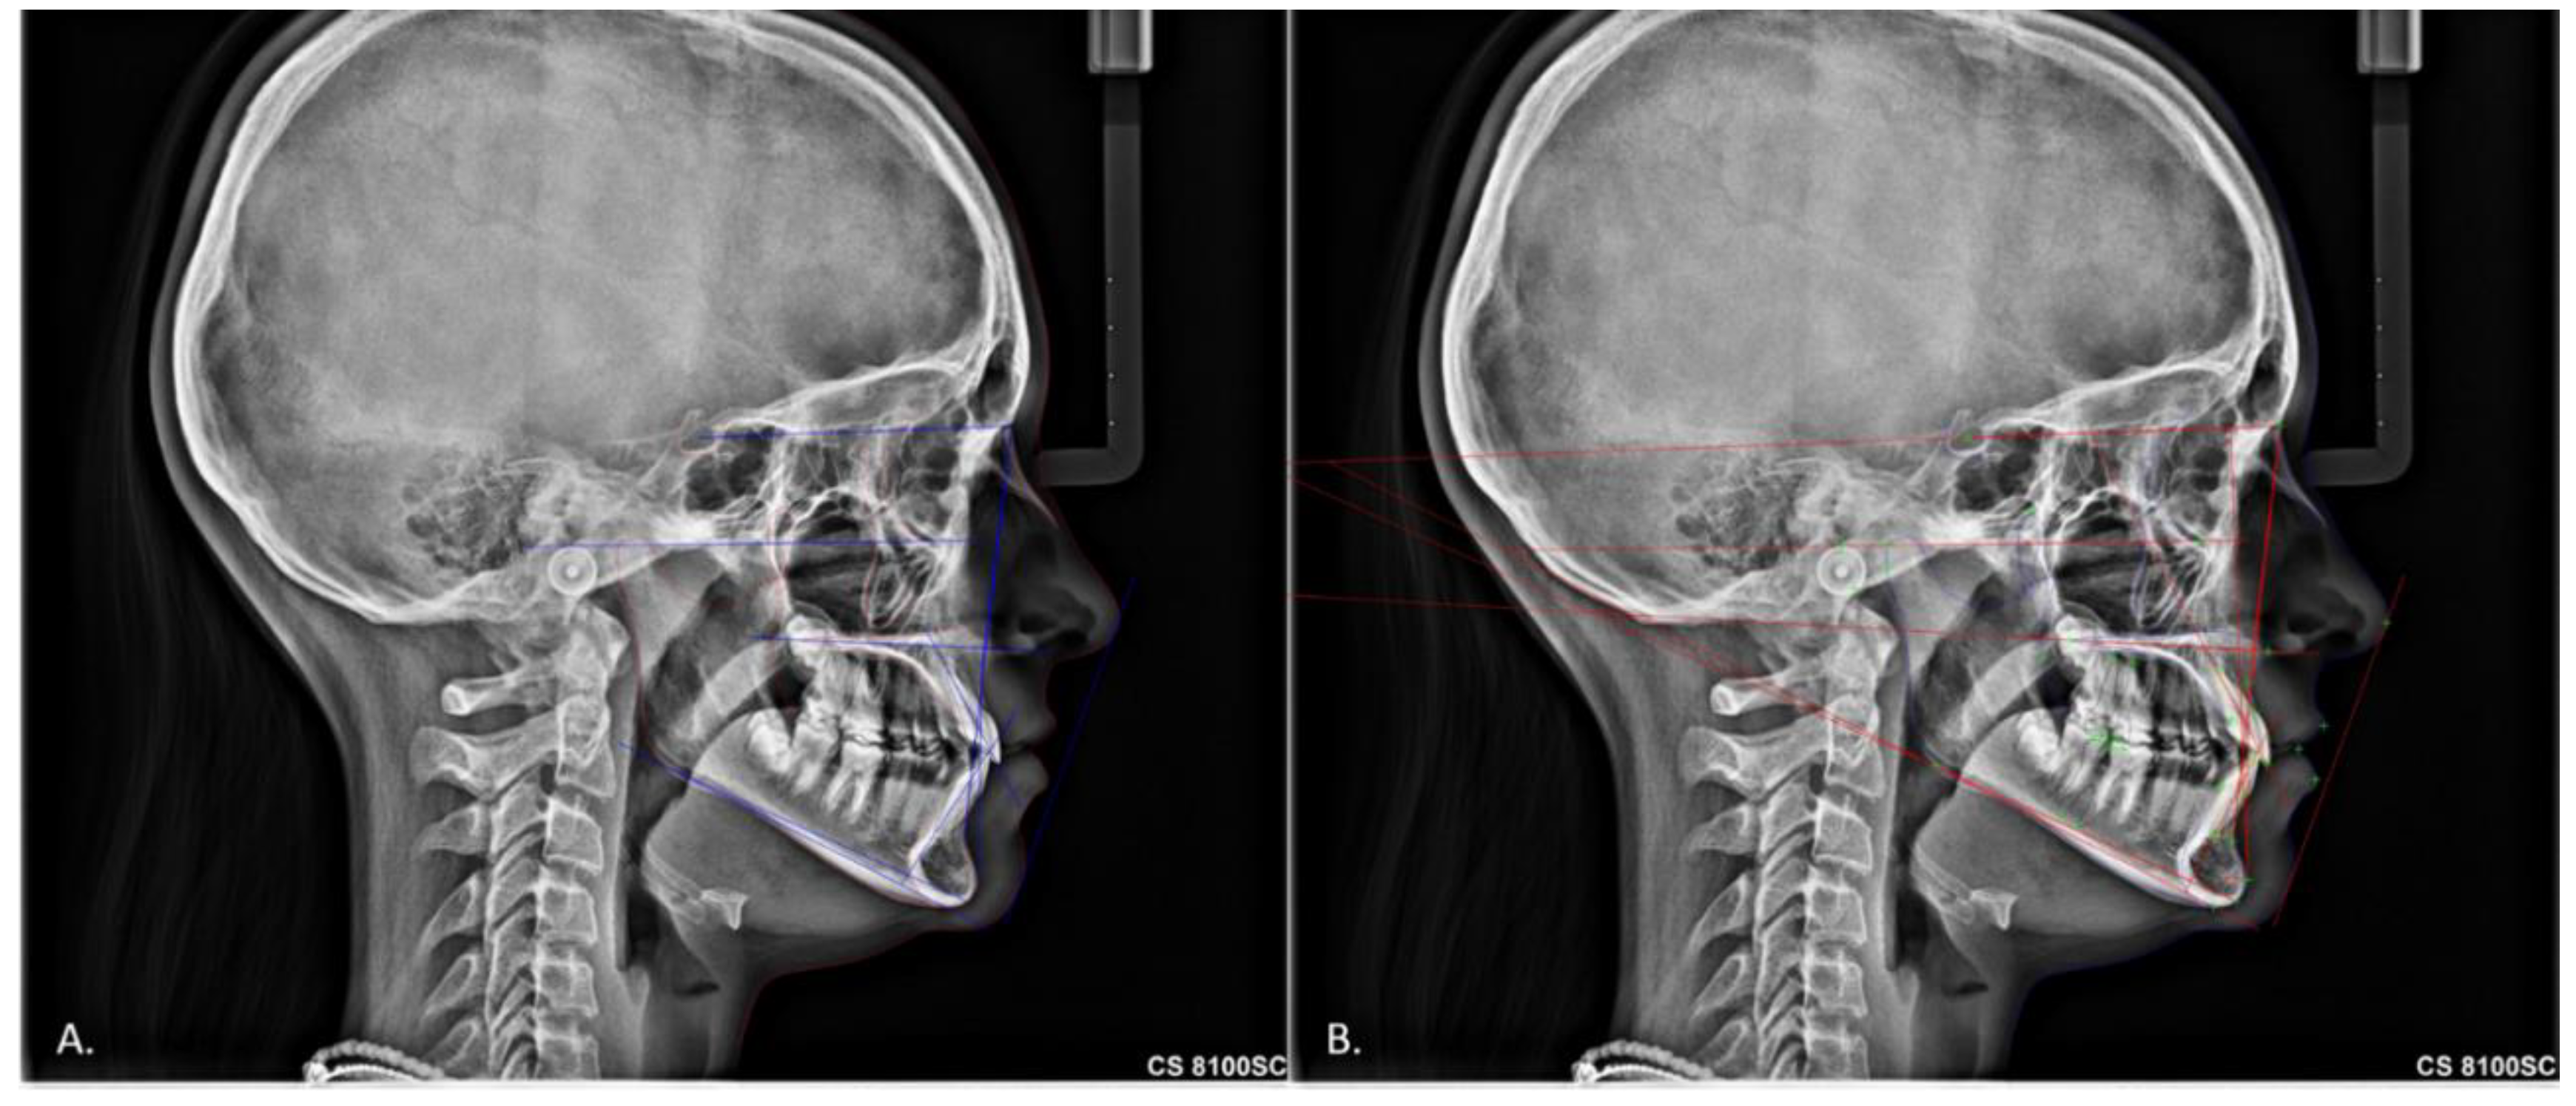

Comparing a Fully Automated Cephalometric Tracing Method to a Manual Tracing Method for Orthodontic Diagnosis

2. Materials and Methods